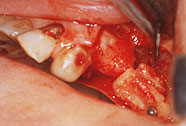

The cortical bone plate of the chin is tried out and adjusted with burrs. If the floor of the sinus is very thin it may be necessary to make an inlay and an onlay at the same time to allow for proper fixation of transplanted bone. The adjusted donor bone is kept in place at or on the floor of the sinus by the use of a 1.5 mm screw fixation (*). The screws are easily removed at the time of implant placement.

The surplus of cortical bone and the harvested bone chips from symphysis and tuberosities are grinded in a bone mill (*). The cortical plate of the antral wall is preserved.